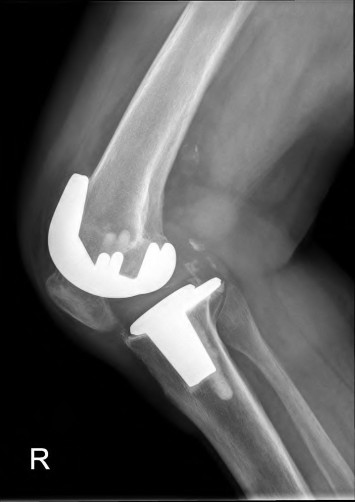

The radiograph demonstrates a periprosthetic femur fracture extending to the tip of the stem. The long spiral fracture is consistent with a loose implant. The bone stock is sufficient. Therefore, this fracture pattern would classify as a B2 using the Vancouver classification system. The Vancouver classification for periprosthetic femoral fractures is simple yet incorporates all the pertinent factors such a location, stem fixation, and bone stock. Type A is a trochanteric fracture- lesser or greater. These can be treated non-operatively usually and ORIF if symptomatic. Type B fractures are around or just below the stem and are subdivided into three types. Type B1 is a fracture with a well fixed stem.

The treatment is cable plating or allograft struts or a combination of the two. Type B2 is a fracture with a loose stem with good bone stock. The treatment is a cementless porous coated long stem atleast two diameter length past the

fracture site. Type B3 is a fracture with a loose stem and comminution. For younger patients, use cementless porous coated long stems with allograft struts. For older patients, consider a tumor prosthesis. Cement fixation is sometimes necessary Type C is a fracture well below the stem tip. These can be treated independently of the prosthesis.